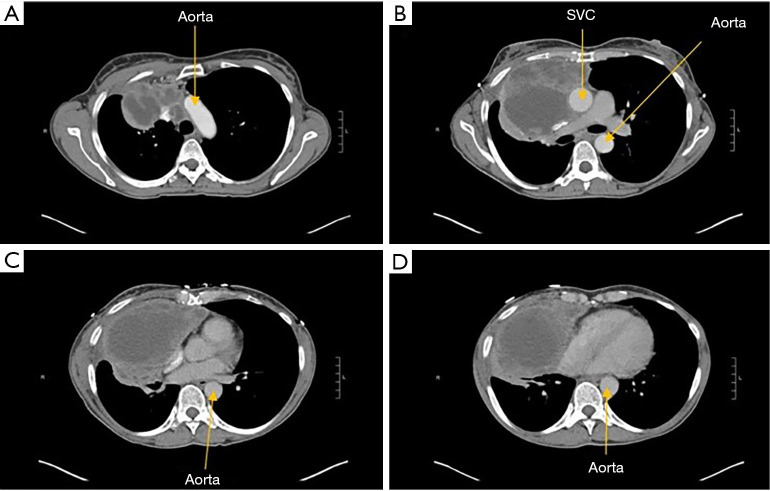

Locally invasive thymic neoplasms are challenging clinical scenarios and typically require a multidisciplinary approach. The involvement of major mediastinal veins such as the superior vena cava (SVC) used to be a contraindication to surgery, but with improved surgical technique and outcomes, this paradigm has shifted. In some situations, complex resections and reconstructions may be indicated and required to improve the long-term outcome of these patients. We report two of our cases along with a current review of literature. We also describe the preoperative workup, operative techniques, postoperative management, complications, and outcomes of patients with invasive thymic neoplasms that involve the mediastinal veins. Our first case describes a patient who was diagnosed with a thymoma extending from the diaphragm to the base of the neck that was also encasing major vascular structures including the SVC and left innominate vein. Our second case describes a patient who was also diagnosed with a large anterior mediastinal mass encasing the great veins and invading the chest wall. We describe the management of these patients and then delve deeper into operative techniques including SVC resection and reconstruction. We describe the types of conduits that can be used and complications to be mindful of when clamping the great veins, such as the SVC. Improvements in conduit materials and neoadjuvant and adjuvant therapies over the years have made it more feasible for patients with invasive thymic neoplasms to undergo surgery.